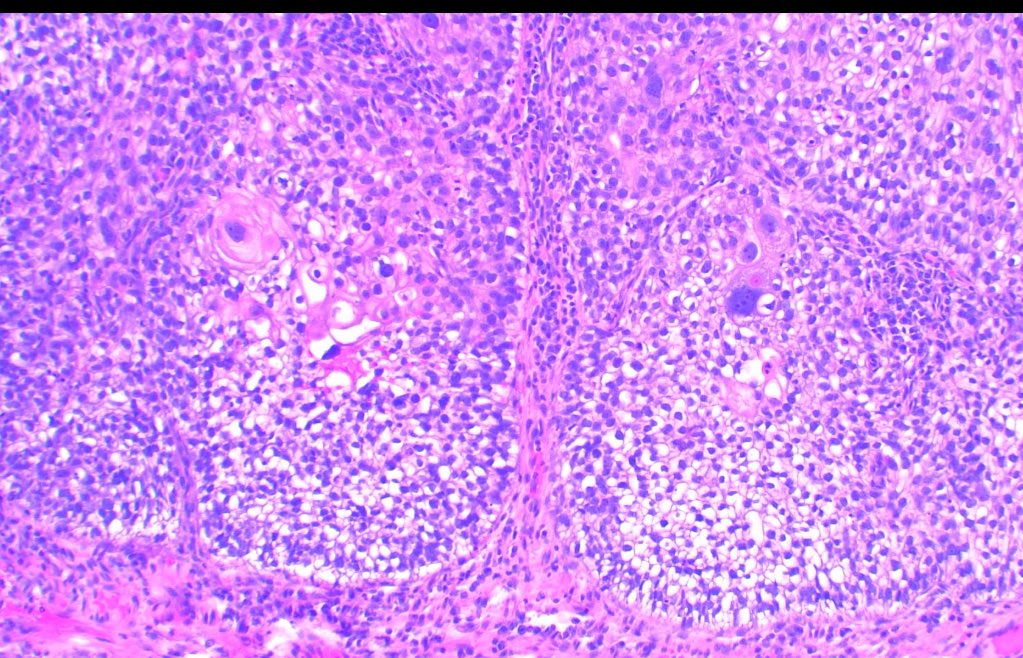

Make the Dx: ASDP October Case Study 85-year-old man with purpuric macules and papules at the abdomen, hips, and bilateral lower legs...… Learn more at asdpcasestudy.secure-platform.com/site/organizat… #asdpcasestudy; #dermatopathology; #dermpath